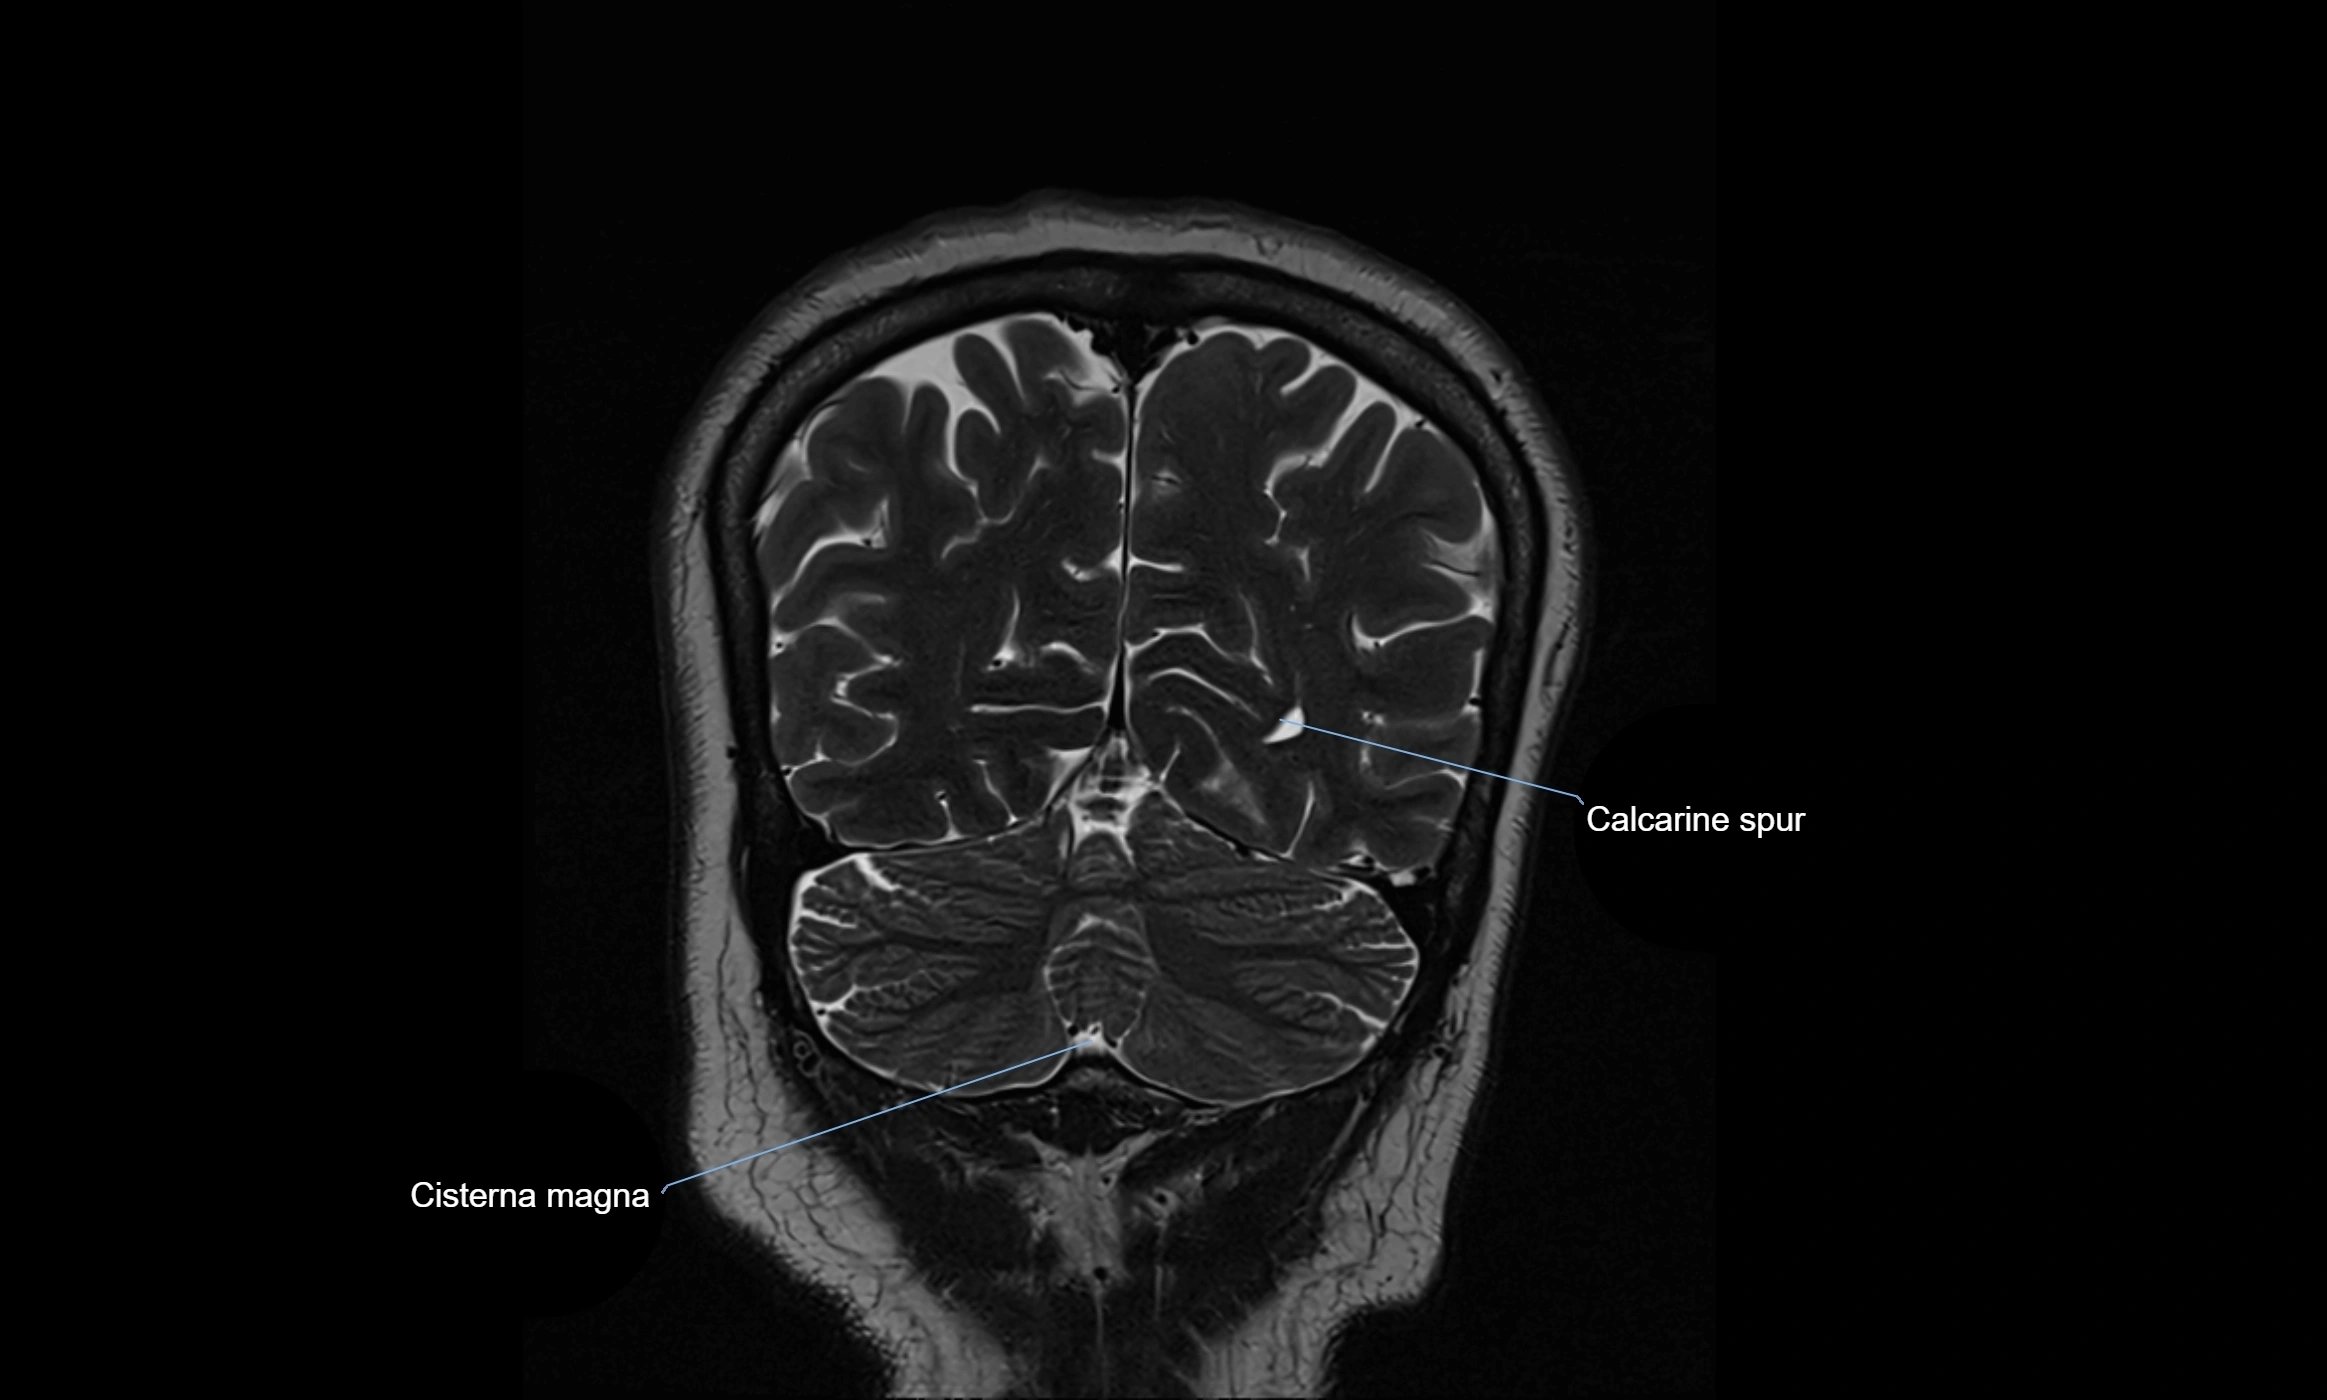

image